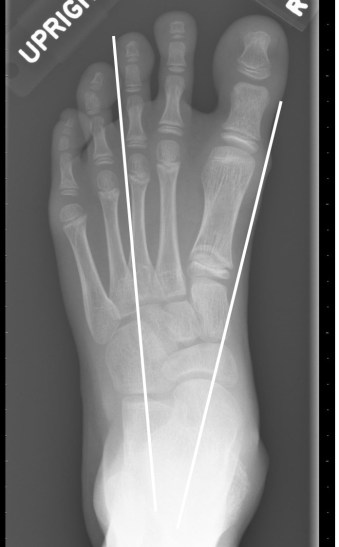

- Talocalcaneal angle: the angle formed between midtalar and midcalcaneal line. Normal: 300-450; <300: varus; >450: valgus.

Midtalar line, midcalcaneal line, and talocalcaneal angle on AP and lateral views

- Valgus: increase in talocalcaneal angle (>450) with midcalcaneal line deviated away from midline.

- Varus: decrease in talocalcaneal angle (<300) with midcalcaneal line deviated towards midline (r in the va’r’us is for ‘reduction’ of angle).

On AP, the midtalar line passes lateral to the base of 1st metatarsal which is abnormal. The midcalcaneal line is passing through the base of 4th metatarsal which is normal. Thus the alignment is abnormal. The talocalcaneal angle is reduced (<30 degrees).

On lateral as well, the talocalcaneal angle is reduced, and the talus appears lifted up by the calcaneus. This is thus a hindfoot varus deformity.